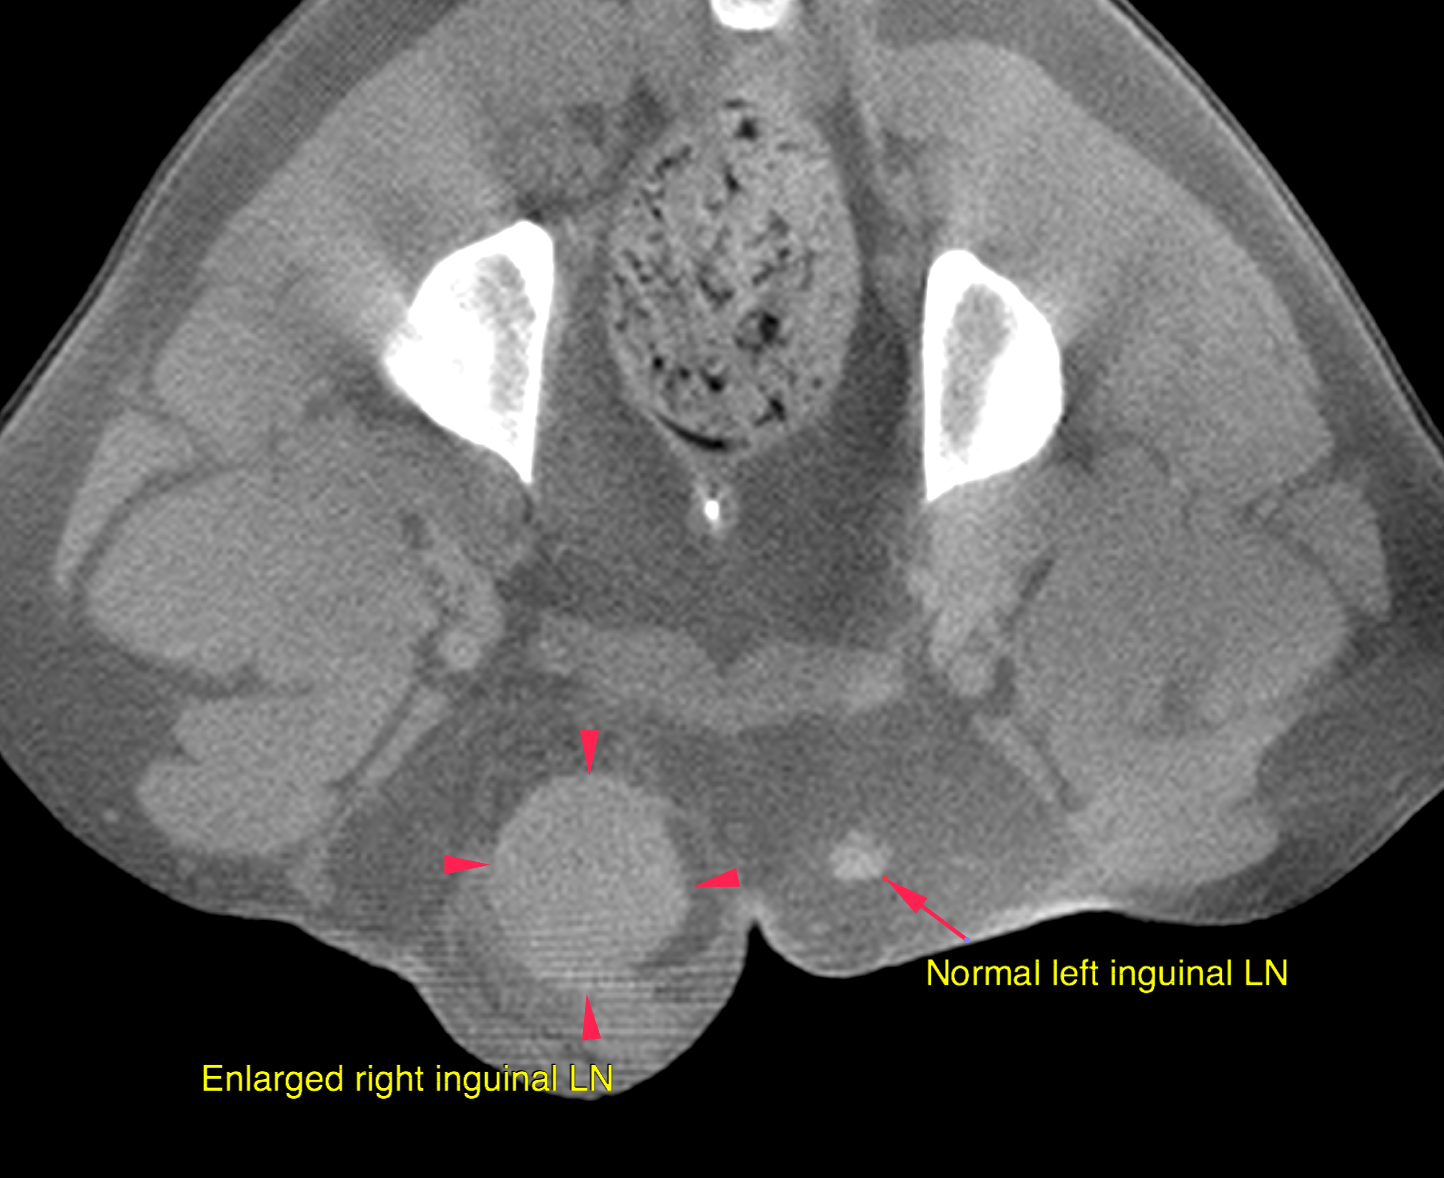

CT – Mast Cell with metastatic spread to right inguinal lymph nodes and tributaries in a 8 year ol FS German Short Haired Pointer

Neoplasia of the right inguinal lymph node meeting malignancy criteria with regional cellulitis

The right inguinal lymph node is severely enlarged at 3 x 2.2 x 6.1 cm with moderate peripheral fat-stranding, increased short-to-long-axis-ratio > 0.5 and irregular contrast enhancement. The right sided tributary lymph nodes (hypogastric, medial iliac and sacral) are markedly enlarged and rounded, short-to-long-axis-ratio > 0.5. The lymph nodes of the hypogastric area on the left side are prominent and rounded as well, short-to-long-axisratio > 0.5. The wall of the vagina/cervix presents moderate focal circumferential and transmural thickening at 1 cm cranial to the vaginal vestibulum.  The spleen is enlarged and rounded

In addition, lymphadenopathy of the hypogastric, medial iliac and sacral lymph-nodes

The findings are consistent with history of mast-cell tumor and metastatic spread to the

right inguinal lymph nodes and its tributaries including the contralateral side. The marked splenomegaly can be either caused by pooling of blood due to general